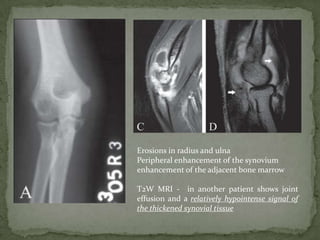

Erosions in radius and ulna

Peripheral enhancement of the synovium

enhancement of the adjacent bone marrow

T2W MRI - in another patient shows joint

effusion and a relatively hypointense signal of

the thickened synovial tissue